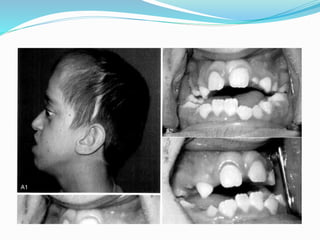

Midface Deficiency

 Frontal bossing

 Petosis

 Dystopy lateral canthal

 Exorbitism-exotropia

 Maxillary hypopalsia

 Maybe hypertelorism

 Tarnsverse deficiency

 C3 malloclusion

 Apertognathia